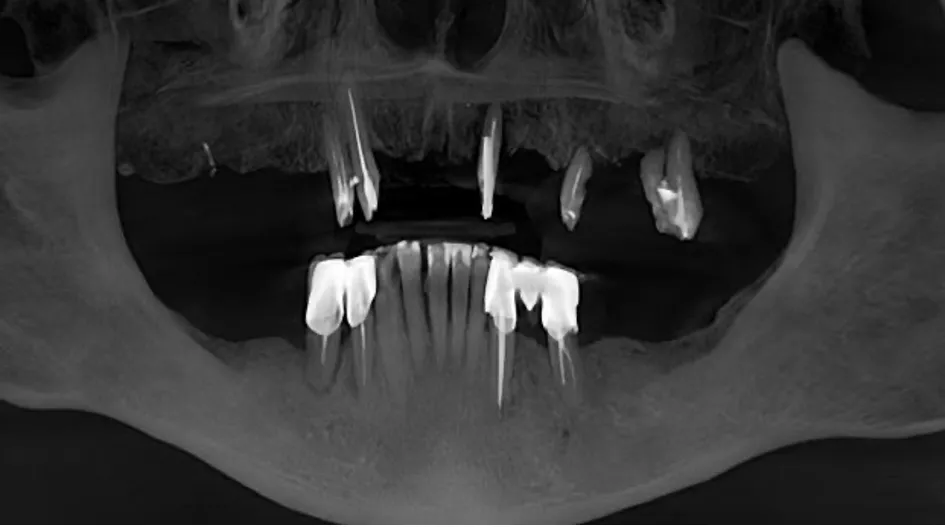

• Radiographic findings: CBCT showed pronounced vertical and horizontal bone resorption in both jaws.

CBCT confirmed pronounced bone resorption in both the maxilla and mandible (Fig. 7).

Fig. 7